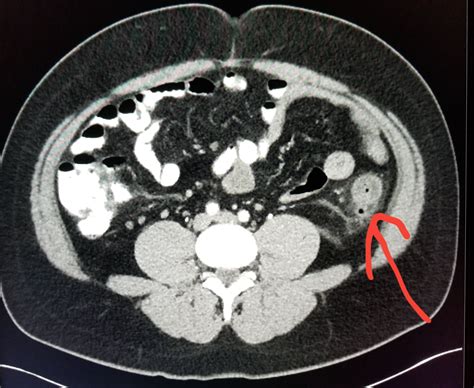

Diverticulitis is a painful condition that occurs when small pouches in the colon, known as diverticula, become inflamed or infected. When a patient presents with symptoms such as severe abdominal pain, fever, and changes in bowel habits, physicians must act quickly to make an accurate diagnosis. Among the various diagnostic tools available in modern medicine, a CT scan for diverticulitis is considered the gold standard. Its ability to provide detailed, cross-sectional images of the abdomen allows healthcare providers to confirm the presence of inflammation, assess the severity of the condition, and rule out other potential causes of abdominal distress.

Once the scan is completed, a radiologist will interpret the images and generate a report. If the scan confirms a diagnosis of diverticulitis, the radiologist will often grade the severity of the disease. This grading system is crucial for determining the appropriate course of treatment. The results of your CT scan for diverticulitis will likely focus on several key indicators:

• Wall Thickening: The degree to which the colon wall has thickened due to inflammation.

• Fat Stranding: A hazy appearance in the fat surrounding the colon, which is a classic sign of localized inflammation.

• Presence of Abscesses: Whether there are pockets of pus that may require drainage or specific antibiotic therapy.

• Free Air: A critical finding that may indicate a perforation, which is a medical emergency requiring immediate surgical consultation.